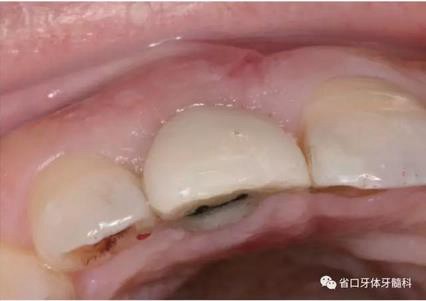

圖1 術(shù)前口內(nèi)照

圖2 術(shù)前口內(nèi)照

圖3 術(shù)前口內(nèi)照

1.?病例簡(jiǎn)介 43歲女性患者,主拆:右上前牙松動(dòng)不適數(shù)日要求修復(fù)。現(xiàn)病史:患者數(shù)年前右上前牙因“齲壞”于外院行根管治療(具體不詳),數(shù)日前牙冠松動(dòng)不適,現(xiàn)覺(jué)影響咀嚼及美觀,遂來(lái)我院要求進(jìn)一步診治。否認(rèn)高血壓、心臟病等重大疾病,否認(rèn)結(jié)核、肝炎等傳染病史,否認(rèn)手 術(shù)、輸血史等,未發(fā)現(xiàn)藥物過(guò)敏。無(wú)吸煙習(xí)慣。臨床檢查:口外觀顏面基 本對(duì)稱,皮膚無(wú)紅腫破潰,顳下頜關(guān)節(jié)區(qū)無(wú)彈響、雜音、壓痛,開(kāi)口度約 37mm,開(kāi)口型“↓”,頜下、刻下和頸部未及腫大淋巴結(jié)。中位笑線??趦?nèi)檢查,口腔衛(wèi)生可,色素(+),BOP(-),PD=2mm,上頜右側(cè)中切 牙冠部變色,冠根折斷至齦下3mm,叩不適,松動(dòng)Ⅱ°~Ⅲ°。牙齦稍紅, 齦緣水平及齦乳頭高度可,屬于中厚齦生物型,附著齦寬度約5mm,唇系帶附著可。上頜右側(cè)中切牙缺牙間隙與對(duì)側(cè)同名牙一致,約>7mm,修復(fù)空 間良好。與對(duì)頜牙覆合覆蓋正常。MCT檢查示上頜右側(cè)中切牙冠根折斷至骨 下,根管內(nèi)見(jiàn)充填物,根充不全,根尖見(jiàn)陰影,大小約3mm×3mm。牙槽窩根方可用骨量可,唇側(cè)骨壁完整,冠方骨壁厚度約1mm。

(1)微創(chuàng)拔牙及即刻種植:術(shù)前拍攝口內(nèi)照及實(shí)施牙周基礎(chǔ)治療。常 規(guī)消毒鋪巾阿替卡因局麻下微創(chuàng)拔除上頜右側(cè)中切牙,搔刮拔牙窩及根尖肉 芽組織。探測(cè)牙槽骨唇側(cè)骨壁及鄰面牙槽嵴完整,牙齦無(wú)撕裂。不翻瓣下于上頜右側(cè)中切牙缺隙近遠(yuǎn)中中點(diǎn)的腭側(cè)牙槽骨及根方定位,按照逐級(jí)預(yù)備的原則,緊貼牙槽窩腭側(cè)骨壁制備種植窩洞,植入Zimer®3.7mm×13mm TSV種植體1顆,植入扭矩>35N·cm,以O(shè)sstell測(cè)量種植體的ISQ值為68。 種植體平臺(tái)位于唇側(cè)齦緣中點(diǎn)下3mm,與唇側(cè)骨壁內(nèi)側(cè)面形成的跳躍間 隙約2mm,置入Bio-Oss®細(xì)顆粒骨粉0.25g,上愈合基臺(tái)關(guān)閉創(chuàng)口。術(shù)后 CBCT檢查顯示:種植體利用牙槽窩根方骨質(zhì)固位,緊貼牙槽窩腭側(cè)骨壁, 其唇側(cè)面與牙槽窩唇側(cè)骨壁的內(nèi)側(cè)面所形成的跳躍間隙(約2mm)可見(jiàn)顆 粒狀顯影物充填。牙槽窩的唇側(cè)骨壁及唇側(cè)倒凹無(wú)缺損穿孔。